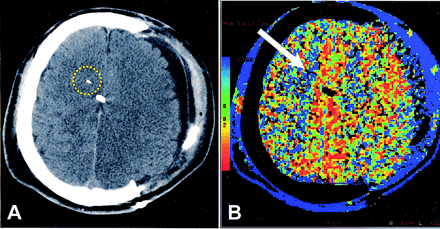

All CT scans were obtained on a single-detector helical scanner (HiSpeed CT/i; GE Medical Systems, Milwaukee, WI). All subjects underwent nonenhanced head CT (axial 5-mm collimation) after placement of a brain-tissue oxygen probe. Because the electrode was visible as a hyperattenuation on CT, the initial images were used to select the level for CTP (Fig 1). Because the oxygen-sensing region spanned 5 mm from the tip of the probe, the axial level corresponding to the most inferior aspect of the probe was used. CTP images were acquired during rapid bolus injection (4 mL/second) of nonionic iodinated contrast agent (Omnipaque 300, 40 mL total; Amersham, Princeton, NJ) via a peripheral (usually forearm) vein. Dynamic (cine) scanning (80 kVp, 200 mA) was repeated at this single axial section (10-mm collimation) after a 5-second delay, for total of 50 images at a rate of one per second. All CTP studies were transferred in DICOM format to an imaging workstation (Advantage Workstation, GE Medical Systems) by means of an optical disk and reviewed by using deconvolution-based CTP analysis software (CT Perfusion2, GE Medical Systems). A single investigator (W.S.S.) who was blinded to brain-tissue oxygen values and other patient characteristics performed all analyses. Standard threshold values in Hounsfield units were used to exclude air and bone (and consequently the metallic tip of the oxygen probe) from analysis. MTT, CBV, and CBF were measured for a standard circular 350-mm2 ROI that encompassed the sensing area of the oxygen probe (Fig 1A). Color maps were created for MTT, CBV, and CBF by using a standard color scale (Fig 1B). For subjects who underwent multiple CT studies after probe placement as part of their regular clinical care, CTP was concurrently performed if possible and the studies included in the dataset.

Patient who underwent hemicraniectomy after head trauma.

A, Nonenhanced CT scan shows the tip of the brain-tissue oxygen probe as a white linear attenuation in the right hemispheric white matter. Midline white attenuation is a ventriculostomy catheter. Yellow circle indicates the ROI for CTP analysis.

B, CTP color map of MTT. On the reference bar, blue indicates the slowest MTT. Arrow points to the tip of the oxygen probe. Overall, MTT is decreased on the side of hemicraniectomy, indicating more rapid transit. Surrounding blue rim represents scalp perfusion.